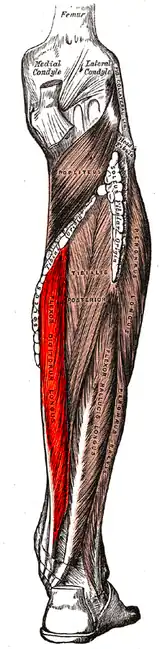

Flexor digitorum longus muscle

The flexor digitorum longus muscle or flexor digitorum communis longus[1] is situated on the tibial side of the leg. At its origin it is thin and pointed, but it gradually increases in size as it descends. It serves to flex the second, third, fourth, and fifth toes.

The flexor digitorum longus muscle arises from the posterior surface of the body of the tibia, from immediately below the soleal line to within 7 or 8 cm of its lower extremity, medial to the tibial origin of the tibialis posterior muscle. It also arises from the fascia covering the tibialis posterior muscle.

The fibers end in a tendon, which runs nearly the whole length of the posterior surface of the muscle. This tendon passes behind the medial malleolus, in a groove, common to it and the tibialis posterior, but separated from the latter by a fibrous septum, each tendon being contained in a special compartment lined by a separate mucous sheath. The tendon of the tibialis posterior and the tendon of the flexor digitorum longus cross each other, in a spot above the medial malleolus, the crural tendinous chiasm.[2][3][4] It passes through the tarsal tunnel.[5]

It passes obliquely forward and lateralward, superficial to the deltoid ligament of the ankle-joint, into the sole of the foot, where it crosses over the tendon of the flexor hallucis longus at the level of the navicular bone at a location known as the knot of henry[6] (also referred to as plantar tendinous chiasm),[2][3][4] and receives from it a strong tendinous slip.

It then expands and is joined by the quadratus plantæ muscle, and finally divides into four tendons, which are inserted into the bases of the last phalanges of the second, third, fourth, and fifth toes, each tendon passing through an opening in the corresponding tendon of the flexor digitorum brevis muscle opposite the base of the first interphalangeal joint.